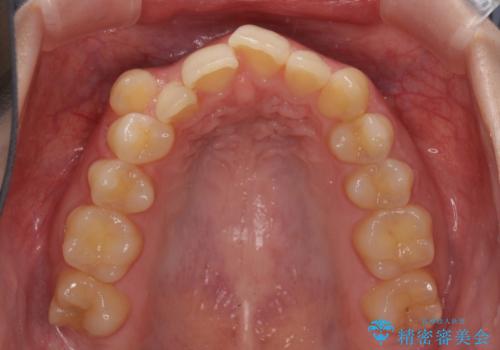

- 著しい八重歯を気にして来院された患者様です。

片側の八重歯であり上顎の正中がずれていたため、上顎左右第一小臼歯2本を抜歯して排列することとしました。

下顎の骨格的なズレが大きかったため、上下歯列のバランスが取れるか心配でしたが、上下ともに左右対称に近い歯列で治療を終えることができました。